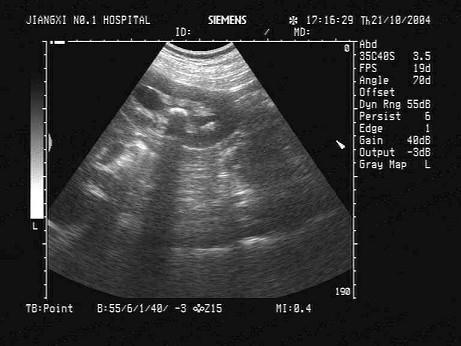

问题 某患者腰部不适,根据其肾脏超声声像图,最可能的诊断为?(?)

选项 A.肾结石并轻度肾积水 B.输尿管结石并肾积水 C.肾积水 D.肾肿瘤 E.肾结石并肾重度积水

答案 A